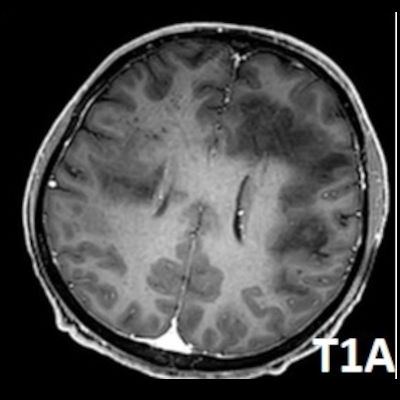

- Bilateral asimetrik subkortikal ve derin beyaz cevherde T1 ağırlıklı görüntülerde belirgin hipointens (oklar), T2A görüntülerde hiperintens (oklar), gri cevhere bakan kesimi düzgün (oklar), DAG’de hiperintens (ok) lezyonlar izlendi. Lezyonlarda T2/FLAIR uyumsuzluğu vardı (ok). Serebellar beyaz cevherde dentat nukleusu koruyan hilal işareti görüldü (ok başı). SWI sekansta sol motor kortekste hipointens kronik glioinflamatuar reaksiyon ile uyumlu sinyal değişikliği izlendi (ok başı).

- Çoğunlukla subkortikal beyaz cevherde ve U fiberlerde, asimetrik, genelde kitle etkisi yapmayan ve kontrastlanmayan demiyelinizan lezyonlar görülür. Korteks ve derin gri cevher tutulumu daha nadirdir.

- PML lezyonları, T1A görüntülerde belirgin hipointenstir. Gri cevhere bakan yüzleri keskin olup T2/FLAIR uyumsuzluğu önemli özelliğidir.